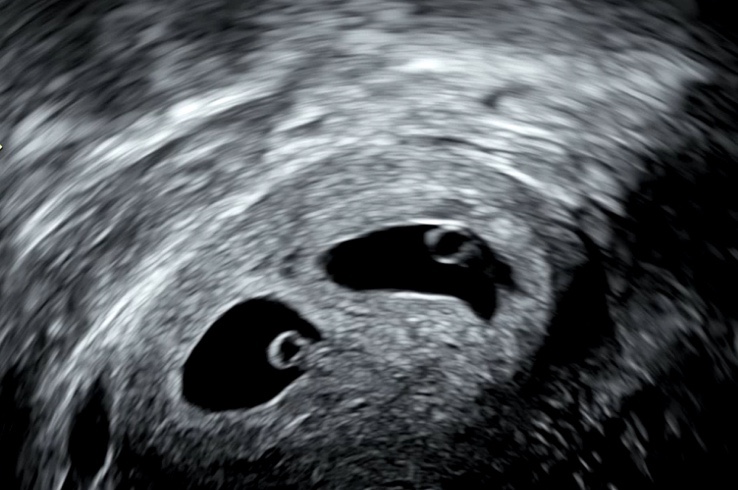

쌍둥이 임신) 5주차-10주차 기록

5주차. 난황이 2개다 난황 2개확인,,,다이아몬드라고 불리는 난황을 보았다 유리구슬같은 느낌이 왜 다이아...